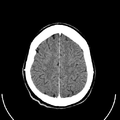

معرض الصور

يوضح ماسح التصوير المقطعي الحاسوبي بدون غلافه كيف يعمل؛ داخل الجهاز الذي يكشف عن داخلك |